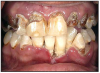

The use of MA has a pattern of damage in the mouth. There are several factors when combined that create an environment that destroys the teeth, the blood supply and supporting tissues. Figures 3 and 4 show two examples of oral destruction MA use can cause.

Figures 3 and 4 Rampant Decay – Photos courtesy of: Sharlee Shirley, RDH, MPH; Jim Cecil, DMD, MPH, University of Kentucky, School of Dentistry United States Department of Justice Meth Awareness Program